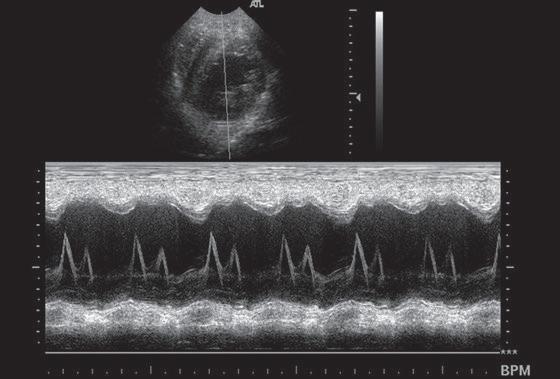

Juan José Esteban Jiménez / Experto Universitario en TC, Experto Universitario en Urgencias de Pequeños Animales y CertSAS / Facultad de Veterinaria de Zaragoza Figura 1. Visión eje corto Ai/Ao. Figura 2. Modo M mitral.

evidencia actual que va quedando claras. En 2020, el estudio DELay dirigido por Borgarelli obtuvo unos resultados muy similares a los encontrados en mi tesis en los que solamente el iECA con espironolactona mostraba eficacia clínica (en estadio B2). Se están poniendo en entredicho valores concretos del ratio Ai/Ao (figura 1), de las medidas ventriculares normalizadas, incluso si es específico de cada raza. Fármacos como el pimobendán parecen tener diferentes semividas en los pacientes, aunque comienza a notificarse que puede ser útil en fases preclínicos, por lo que queda mucho terrero por estudiar.